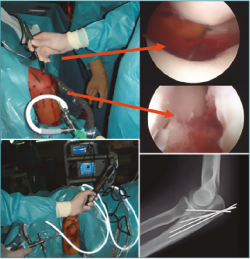

El uso del artroscopio como complemento para el tratamiento de las fracturas articulares –rodilla y muñeca especialmente– es una práctica generalizada en muchos servicios de traumatología, pero en la actualidad su uso sigue siendo infrecuente para las fracturas del área del codo (Figura 1).

Figura 1. Fractura de codo asistida por artroscopia.

Nuestra experiencia durante el periodo 2007-2017 es de 110 artroscopias de codo, realizadas en distintos centros sanitarios (sanidad pública y privada). Si bien algunas indicaciones han sido las clásicas (extracción de cuerpos libres, epicondilalgias, artrolisis, valoración de osteocondritis disecante, biopsia sinovial y sinovectomía, así como el diagnóstico de condromatosis sinovial), desde hace años valoramos la inestimable ayuda del artroscopio para las fracturas articulares de esta compleja articulación (Figura 1).